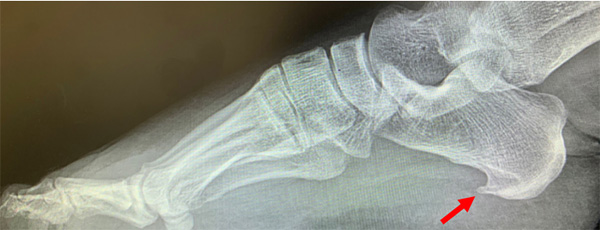

● X光片可以看到跟腱止点区域骨质增生,跟腱内钙化;